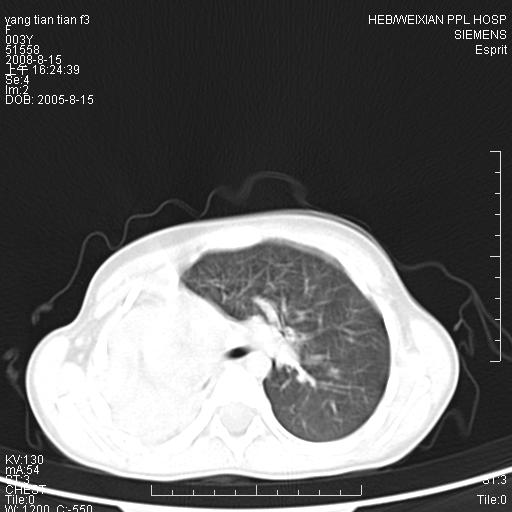

患儿,女,5岁,平素活动后气短,左侧面瘫.右侧胸廓较左侧塌陷.

两侧胸廓不甚对称,左侧稍膨隆,右肺体积明显变小,密度增高,未见正常通气肺组织,纵隔结构明显右移,心脏边缘欠清,外形似增大。纵隔血管间隙不清晰,左肺外形增大,部分肺组织突向右侧胸腔,左肺内未见异常密度影,右侧支气管逐渐变细,其内未见异常密度影。右侧未见叶及段支气管。右侧膈肌升高。

1。右肺体积小(考虑右肺发育不全)

2。左肺代偿性增大

3。心影增大?